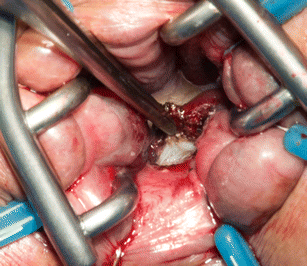

Sparing the extrinsic autonomic innervation of the internal anal sphincter during total mesorectal excision is important for the preservation of anal sphincter function. This study electrophysiologically confirmed the topography of the internal anal sphincter nerve supply during laparoscopic-assisted transanal minimally invasive surgery for total mesorectal excision.

This prospective study was conducted at two large multispecialty referral centers. Six patients (five males and one female) aged between 45 and 65 years with low rectal cancer (≤5 cm from the anal verge) were enrolled. Surgery was performed under electric stimulation of the pelvic autonomic nerves with observation of the electromyographic signals of the internal anal sphincter.

The minimally invasive transanal surgical approach enabled advantageous visualization of the pelvic autonomic nerves in all patients. In particular, extrinsic innervation to the internal anal sphincter near the levator muscle was consciously spared under electrophysiological confirmation. The evoked absolute electromyographic amplitudes of the internal anal sphincter during transanal minimally invasive surgery were significantly lower than the initial results of the laparoscopic approach [3.7 μV (interquartile range 2.4; 5.7) vs. 4.3 μV (interquartile range 3.1; 8.6); p = 0.002]. Five key zones of risk for pelvic autonomic nerve damage were identified. No complications occurred.

The electromyographic results of this preliminary study indicate advantages for sparing the internal anal sphincter innervation during transanal minimally invasive mesorectal dissection considering the specific in situ neuroanatomical topography.